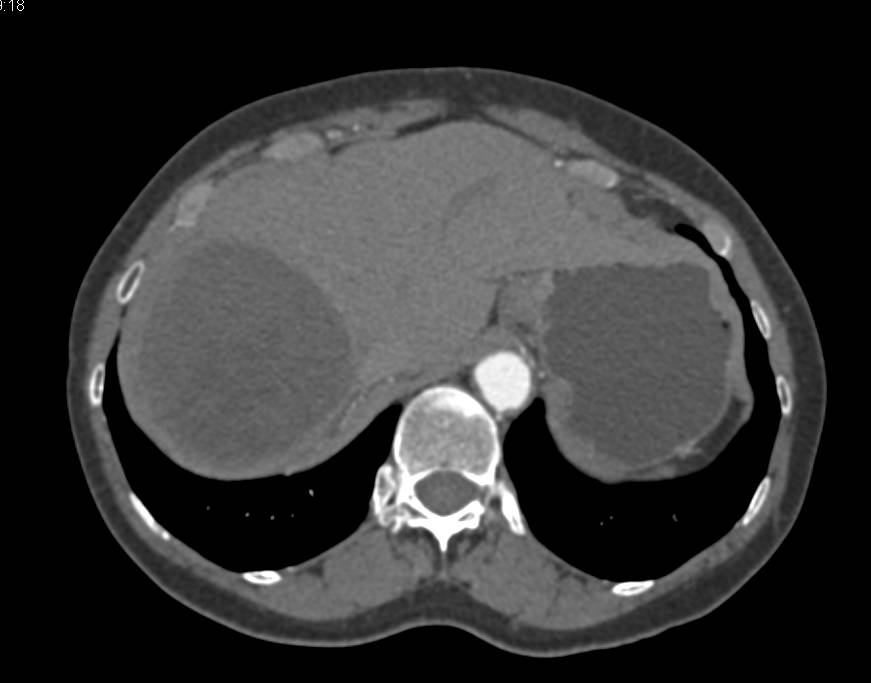

CT scan showing hepatic multiple cysts. Download Scientific Diagram Can You See A Cyst On A Ct Scan They are usually benign (noncancerous) and often form on the skin due to an infection, or clogged oil glands. The test can help tell if ovarian cancer has spread to other. It often means the radiologist has detected a benign cyst in an organ. Cysts are very common and are water containing structure’s that are usually of no concern at. Can You See A Cyst On A Ct Scan.